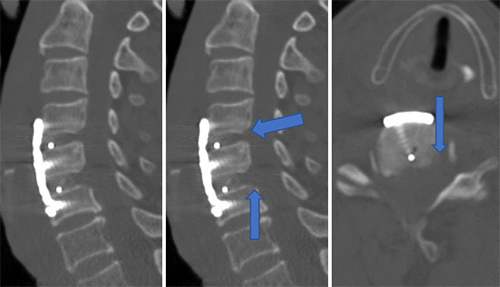

(三)充分减压